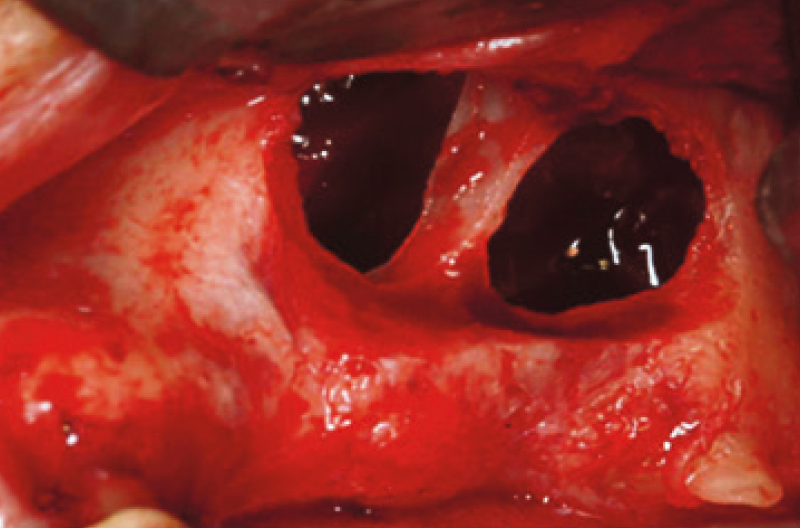

Ugualmente, nel caso di una comunicazione oro-sinusale (COS) e di una fistola oro-sinusale bisognerà ricostituire l’integrità anatomica delle due strutture (cavità sinusale, cavità orale) prima di attuare altro trattamento (Figg. 2, 3).

Fig. 2 – Apertura di lembo peduncolato a tutto spessore, comprendente lo sbocco fistoloso, ed evidenziazione della comunicazione oro-sinusale